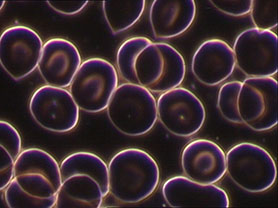

Die Dunkelfeldmikroskopie des Lebendblutes gibt uns Einblick in die innere Welt und zeigt, wie das Milieu beschaffen ist. Dieses Diagnoseverfahren gibt Auskunft darüber, ob ein Organismus sich in einem gesunden Gleichgewicht befindet oder nicht. Ist das Milieu stimmig und ausgewogen, ist der Körper in der Lage, mit einer bestimmten Anzahl an pathogenen (krankmachenden) Faktoren zu leben. Dank seiner guten Regulationsfähigkeit kann er auf pathogene Reize schnell reagieren, so dass diese vom Gesamtsystem eliminiert werden können, und der Mensch gesund, vital und leistungsfähig bleibt.

Bei der Dunkelfeldmikroskopie wird aus der Fingerbeere ein Tropfen Blut entnommen und unter 1000-facher Vergrößerung betrachtet. Das Objekt wird von seitlich unten bestrahlt, so dass der Hintergrund dunkel erscheint und auch kleinste Strukturen im Plasma noch gut erkannt werden können.